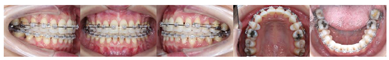

像5).第27个月矫治结束,上下颌压膜保持器保持,定期复查(图4)。

像矫治结束后面像显示患者侧貌改善明显,鼻唇角恢复正常,颏部形态有所改善。口内像显示上下前牙覆

覆盖正常,中线对齐,双侧尖牙中性关系、磨牙完全远中关系,尖窝交错,缺牙间隙关闭未见明显龈退缩。曲断片37、38、47、48得到直立牙根平行较好,未发现明显的牙根吸收和齿槽嵴骨吸收的情况。临床检查下前牙区有少量龈退缩及牙龈黑三角情况(图5)。保持期追踪显示牙齿咬合排列保持良好拥挤间隙未见复发,缺牙间隙闭合紧密,面型良好(图6)。治疗前后的锥形束CT对比显示,植骨区域牙槽骨宽度有显著增加,移入缺隙内的下颌第二磨牙及第二前磨牙未见骨开窗骨开裂(图7)。